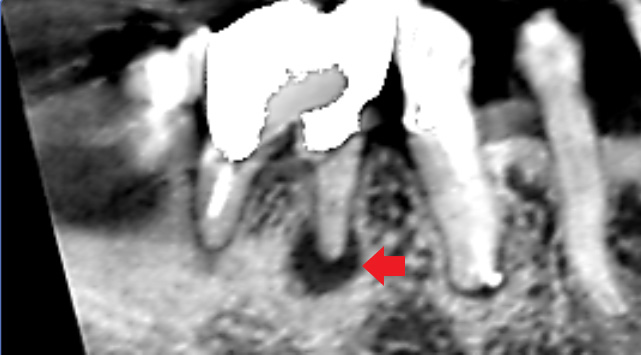

下の画像は、根管治療されていた大臼歯の初診時のCT画像です。根の先には根尖病変の炎症像は特にみられませんでした。他の歯の治療後の経過観察中に膿ができてきたケースです。根管治療が必要になったので、通法通り再根管治療を行い、膿は改善しました。